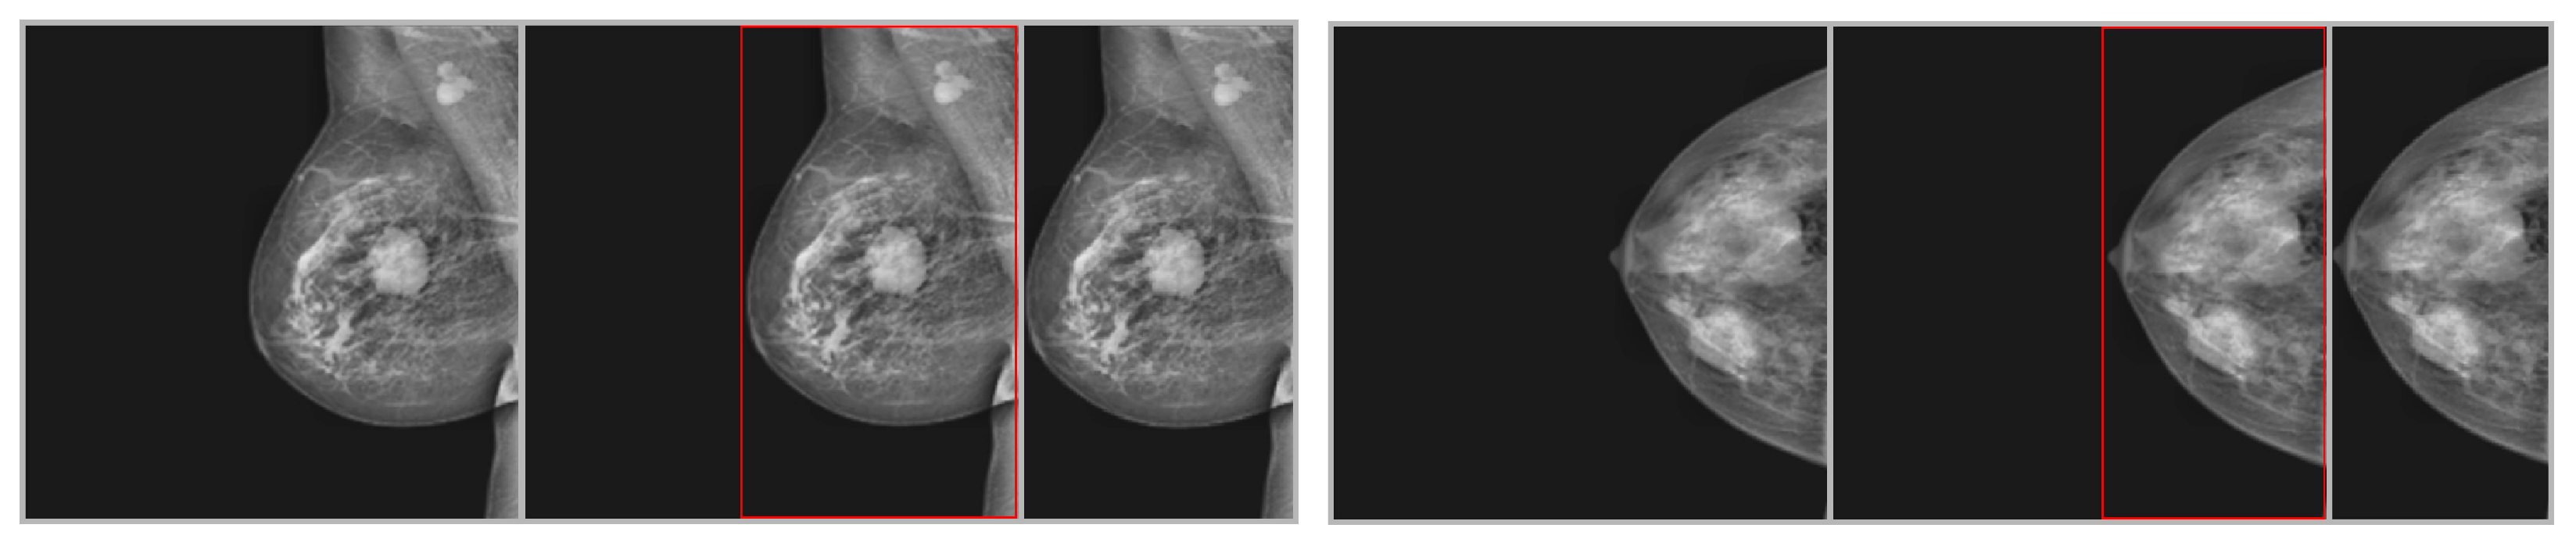

This research utilized mammogram images from three publicly available datasets: MIAS, DDSM, and INbreast. DDSM is a curated subgroup of regular DDSM (Digital Database for Screening Mammograms) and contains different breast imagery samples. The INbreast dataset blends several FFDMs (Full Field Digital Mammograms). The samples of the INbreast dataset provide more useful facts than the mammogram images of the DDSM database. The researchers also commonly use the MIAS dataset, which has 322 mammogram images of size. This dataset includes aberrant and normal photos. The two types of abnormal images are benign and malignant. This study utilized a total of 1572 original mammography images from three benchmark datasets: 300 photos from MIAS (39 malignant, 52 benign, 209 normal), 1194 images from DDSM (637 malignant, 557 benign), and 152 images from INbreast (70 malignant, 76 benign). The data were randomly and equitably divided into training and testing sets, maintaining class balance by stratified sampling. The utilization of these datasets shows that they are very famous in the breast cancer research community and considered standard for assessing models. Sample images from selected datasets for malignant and benign classes are shown in Figure 1, whereas the summary of each dataset is presented in Table 3.

Figure 1.

Sample images of each dataset from both malignant and benign classes.